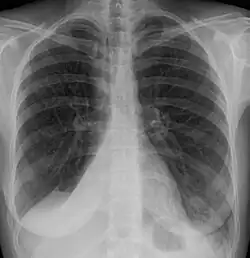

| Atelectasis of a person's right lung | |

Atelectasis is the partial collapse or closure of a lung resulting in reduced or absence in gas exchange. It is usually unilateral, affecting part or all of one lung.[2] It is a condition where the alveoli are deflated down to little or no volume, as distinct from pulmonary consolidation, in which they are filled with liquid. It is often referred to informally as a collapsed lung, although more accurately it usually involves only a partial collapse, and that ambiguous term is also informally used for a fully collapsed lung caused by a pneumothorax.[1]

It is a very common finding in chest X-rays and other radiological studies, and may be caused by normal exhalation or by various medical conditions. Although frequently described as a collapse of lung tissue, atelectasis is not synonymous with a pneumothorax, which is a more specific condition that can cause atelectasis. Acute atelectasis may occur as a post-operative complication or as a result of surfactant deficiency. In premature babies, this leads to infant respiratory distress syndrome.

Clinically significant atelectasis is generally visible on chest X-ray; findings can include lung opacification and/or loss of lung volume. Post-surgical atelectasis will be bibasal in pattern. Chest CT or bronchoscopy may be necessary if the cause of atelectasis is not clinically apparent. Direct signs of atelectasis include displacement of interlobar fissures and mobile structures within the thorax, overinflation of the unaffected ipsilateral lobe or contralateral lung, and opacification of the collapsed lobe. In addition to clinically significant findings on chest X-rays, patients may present with indirect signs and symptoms such as elevation of the diaphragm, shifting of the trachea, heart and mediastinum; displacement of the hilus and shifting granulomas.[13]